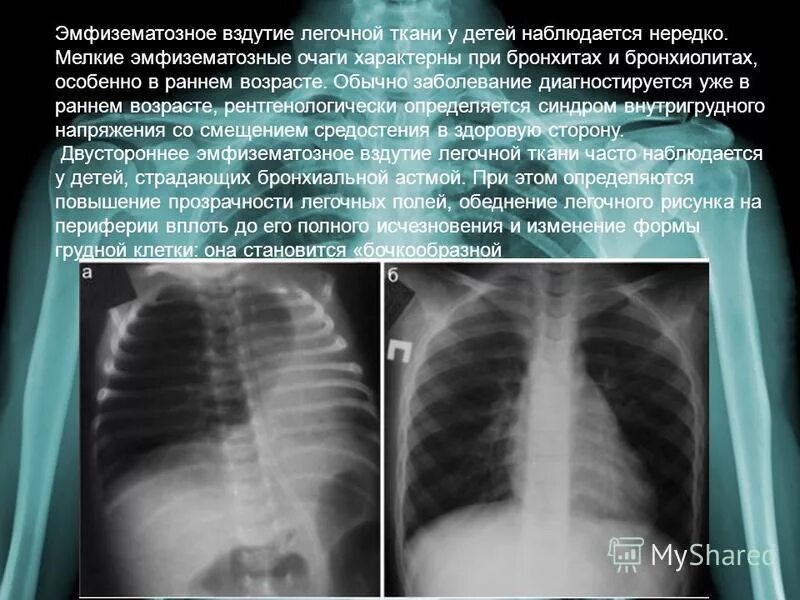

Изменение в легких у ребенка